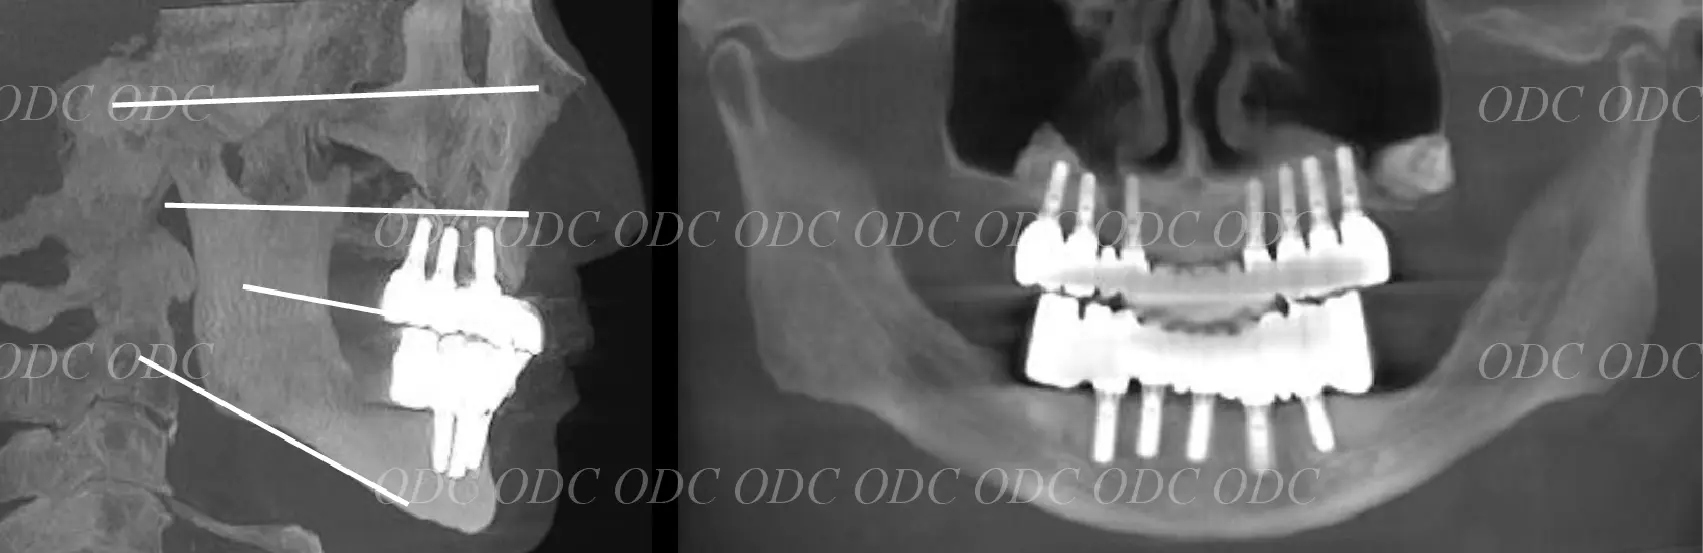

顎関節等の噛み合わせ治療を併用して上下固定式のインプラント治療を終了。

上顎には第3世代ジルコニアの上部構造、下顎には第2世代セラミックの上部構造を装着。

タカギインデックスより計算された咬合平面を設定しているため、噛み合わせはとても安定しております。

治療終了より約11年経過しましたが現在も問題なく使用されています。

サイナスリフトした骨も全てのインプラント体も安定しております。